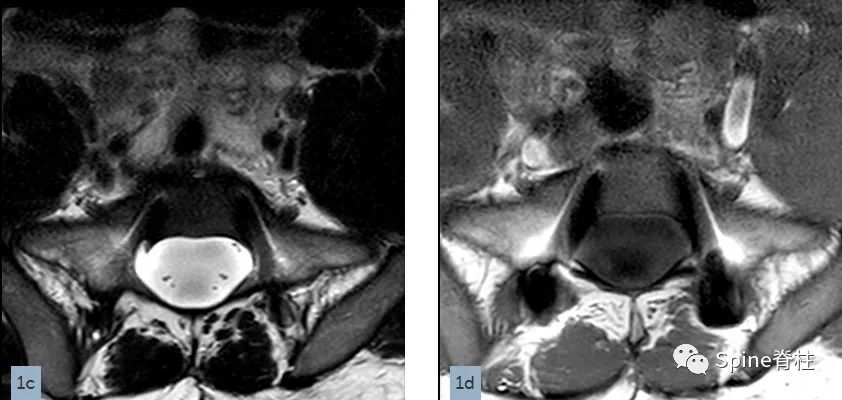

一名18岁男性因腰痛接受MRI检查,下图为矢状位T2(1a)和T1加权像(1b)、S1水平横断面T2(1c)和T1加权像(1d)。

有什么发现?

您的诊断是?